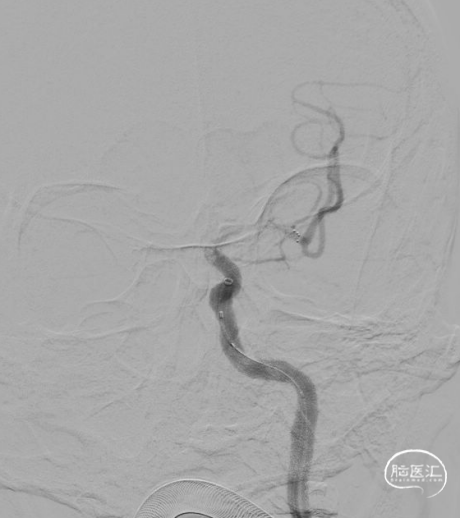

至支架与血栓充分嵌合后,支架锚定下将6F 125cm 通桥银蛇®颅内支持导管向前送至大脑中动脉M1段起始部血栓近端,回撤微导管及支架系统,同时中间导管尾端行负压抽吸回撤,取出大量血栓;即刻造影见左侧颈内动脉大脑中动脉系统血流恢复,远端血流mTICI 3级。

术后24小时复查头颅CT未见出血,CTA提示血管通畅。予加用氯吡格雷单抗抗血小板聚集。